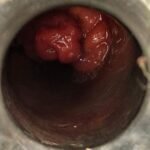

LASER LIAS FOR ANAL FISSURES AND BANDING OF HEMORRHOIDS